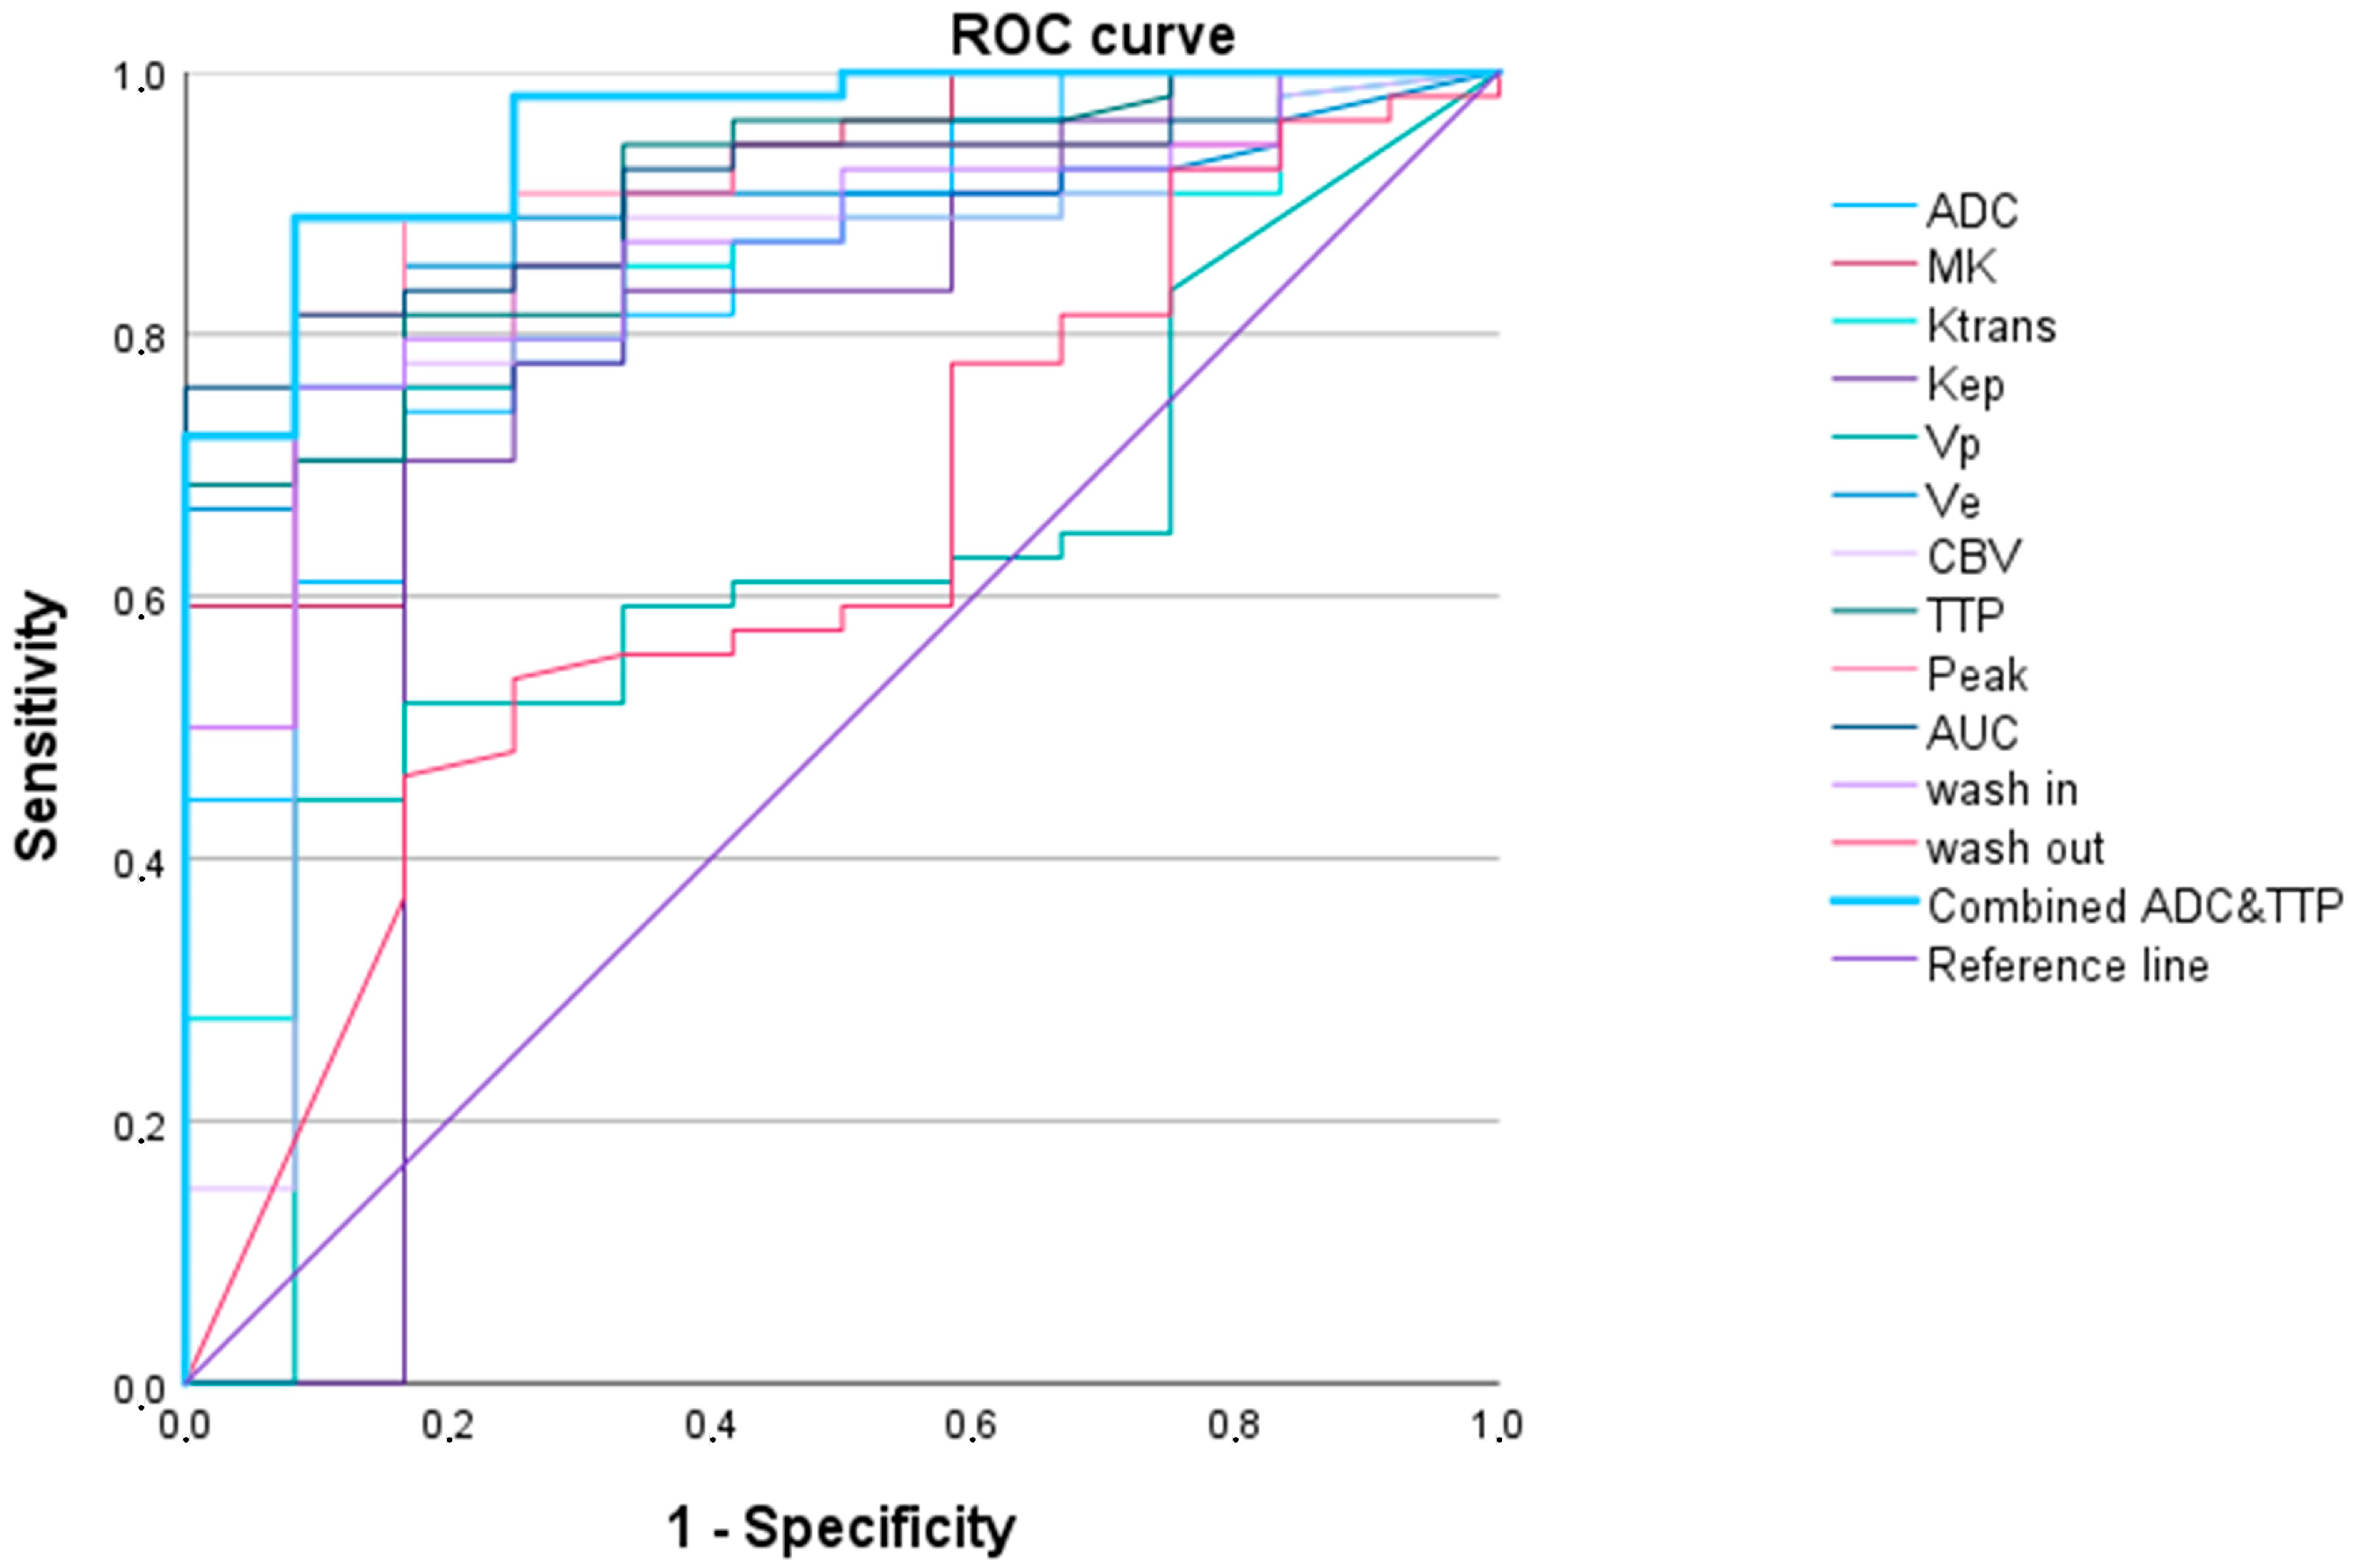

3.2.1. LGG versus HGG

| WHO Grade 2 vs. WHO Grades 3 and 4 Adult-Type Gliomas | ||||||

|---|---|---|---|---|---|---|

| AUC (95% Confidence Interval) | p-Value | Cut-Off Value 1 | Sensitivity | Specificity | AIC | |

| Ktrans | 0.819 (0.695–0.944) | 0.001 | 1083.0 | 0.704 | 0.917 | 50.101 |

| Kep | 0.738 (0.538–0.938) | 0.010 | 388.4 | 0.704 | 0.833 | 53.158 |

| Vp | 0.610 (0.445–0.775) | 0.235 | 1272.1 | 0.444 | 0.917 | 62.937 |

| Ve | 0.885 (0.803–0.967) | <0.001 | 133.4 | 0.852 | 0.833 | 40.898 |

| CBV | 0.821 (0.682–0.960) | 0.001 | 827.9 | 0.778 | 0.833 | 50.917 |

| TTP | 0.902 (0.822–0.982) | <0.001 | 1769.4 | 0.685 | 1.000 | 43.158 |

| Peak | 0.895 (0.804–0.986) | <0.001 | 11.9 | 0.889 | 0.883 | 41.096 |

| AUCDCE | 0.910 (0.840–0.980) | <0.001 | 76.2 | 0.759 | 1.000 | 37.911 |

| wash in | 0.860 (0.761–0.958) | <0.001 | 13,334.5 | 0.759 | 0.917 | 45.400 |

| wash out | 0.631 (0.461–0.801) | 0.158 | 4.3 | 0.463 | 0.833 | 60.495 |

| ADC | 0.844 (0.732–0.956) | <0.001 | 542.1 | 0.741 | 0.833 | 48.012 |

| MK | 0.884 (0.788–0.981) | <0.001 | 551.5 | 0.852 | 0.750 | 41.893 |

| TTP and ADC 2 | 0.954 (0.900–1.000) | <0.001 | 0.8 | 0.889 | 0.917 | 28.532 |